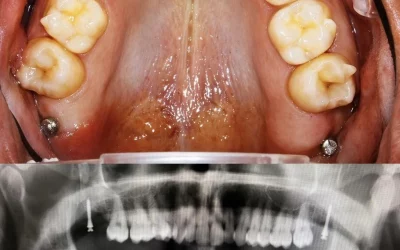

MARPE y alineadores: todo lo que debes saber para una correcta planificación

La expansión palatina asistida por microtornillos (MARPE) se ha convertido en una de las herramientas más potentes para corregir discrepancias esqueléticas transversales en adolescentes tardíos y adultos jóvenes. En una época en la que la estética y la comodidad...